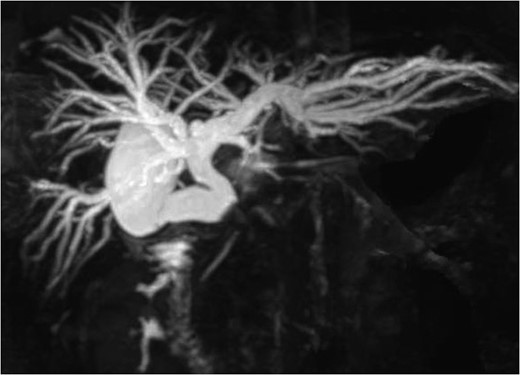

Before surgery, the stent tube was changed to an endoscopic nasobiliary drainage (ENBD) tube for intraoperative cholangiography. The initial intraoperative examination revealed the marked thickening of the gallbladder wall. First, the anterior wall of Hartmann’s pouch was excised to remove the impacted gallstone (Fig. 3). After the removal of the gallstone, a cholecystocholedochal fistula was identified. The gallbladder was then excised and the remaining neck portion was used to perform choledochoplasty using a gallbladder patch. The gallbladder patch was sutured to cover the anterior wall of the common hepatic bile duct (Fig. 4). Intraoperative cholangiography was performed to confirm the absence of bile leakage and bile duct stenosis.

The intraoperative findings: The gallbladder patch was sutured to the dilated cystic duct and intraoperative cholangiography was performed.